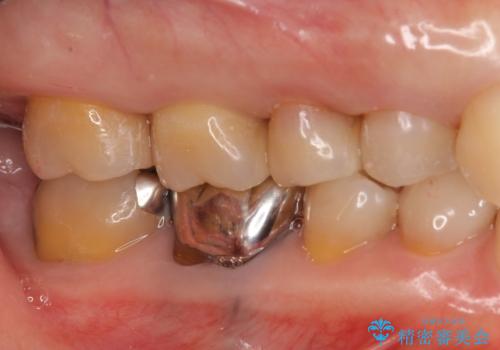

銀歯を白く 虫歯治療

- 虫歯治療を希望して来院。

保険適用の銀色のつめもののやり替えを行いました。

- 30.8万円(右上4567 emaxプレスインレー 7万円x4本)費用は治療当時の料金となります